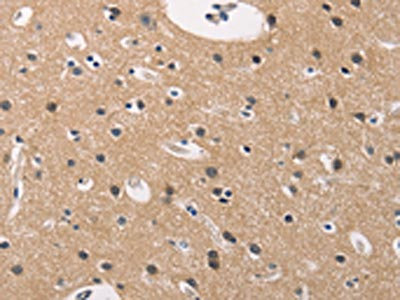

The image on the left is immunohistochemistry of paraffin-embedded Human brain tissue using CSB-PA172172(BAI1 Antibody) at dilution 1/40, on the right is treated with synthetic peptide. (Original magnification: ×200)